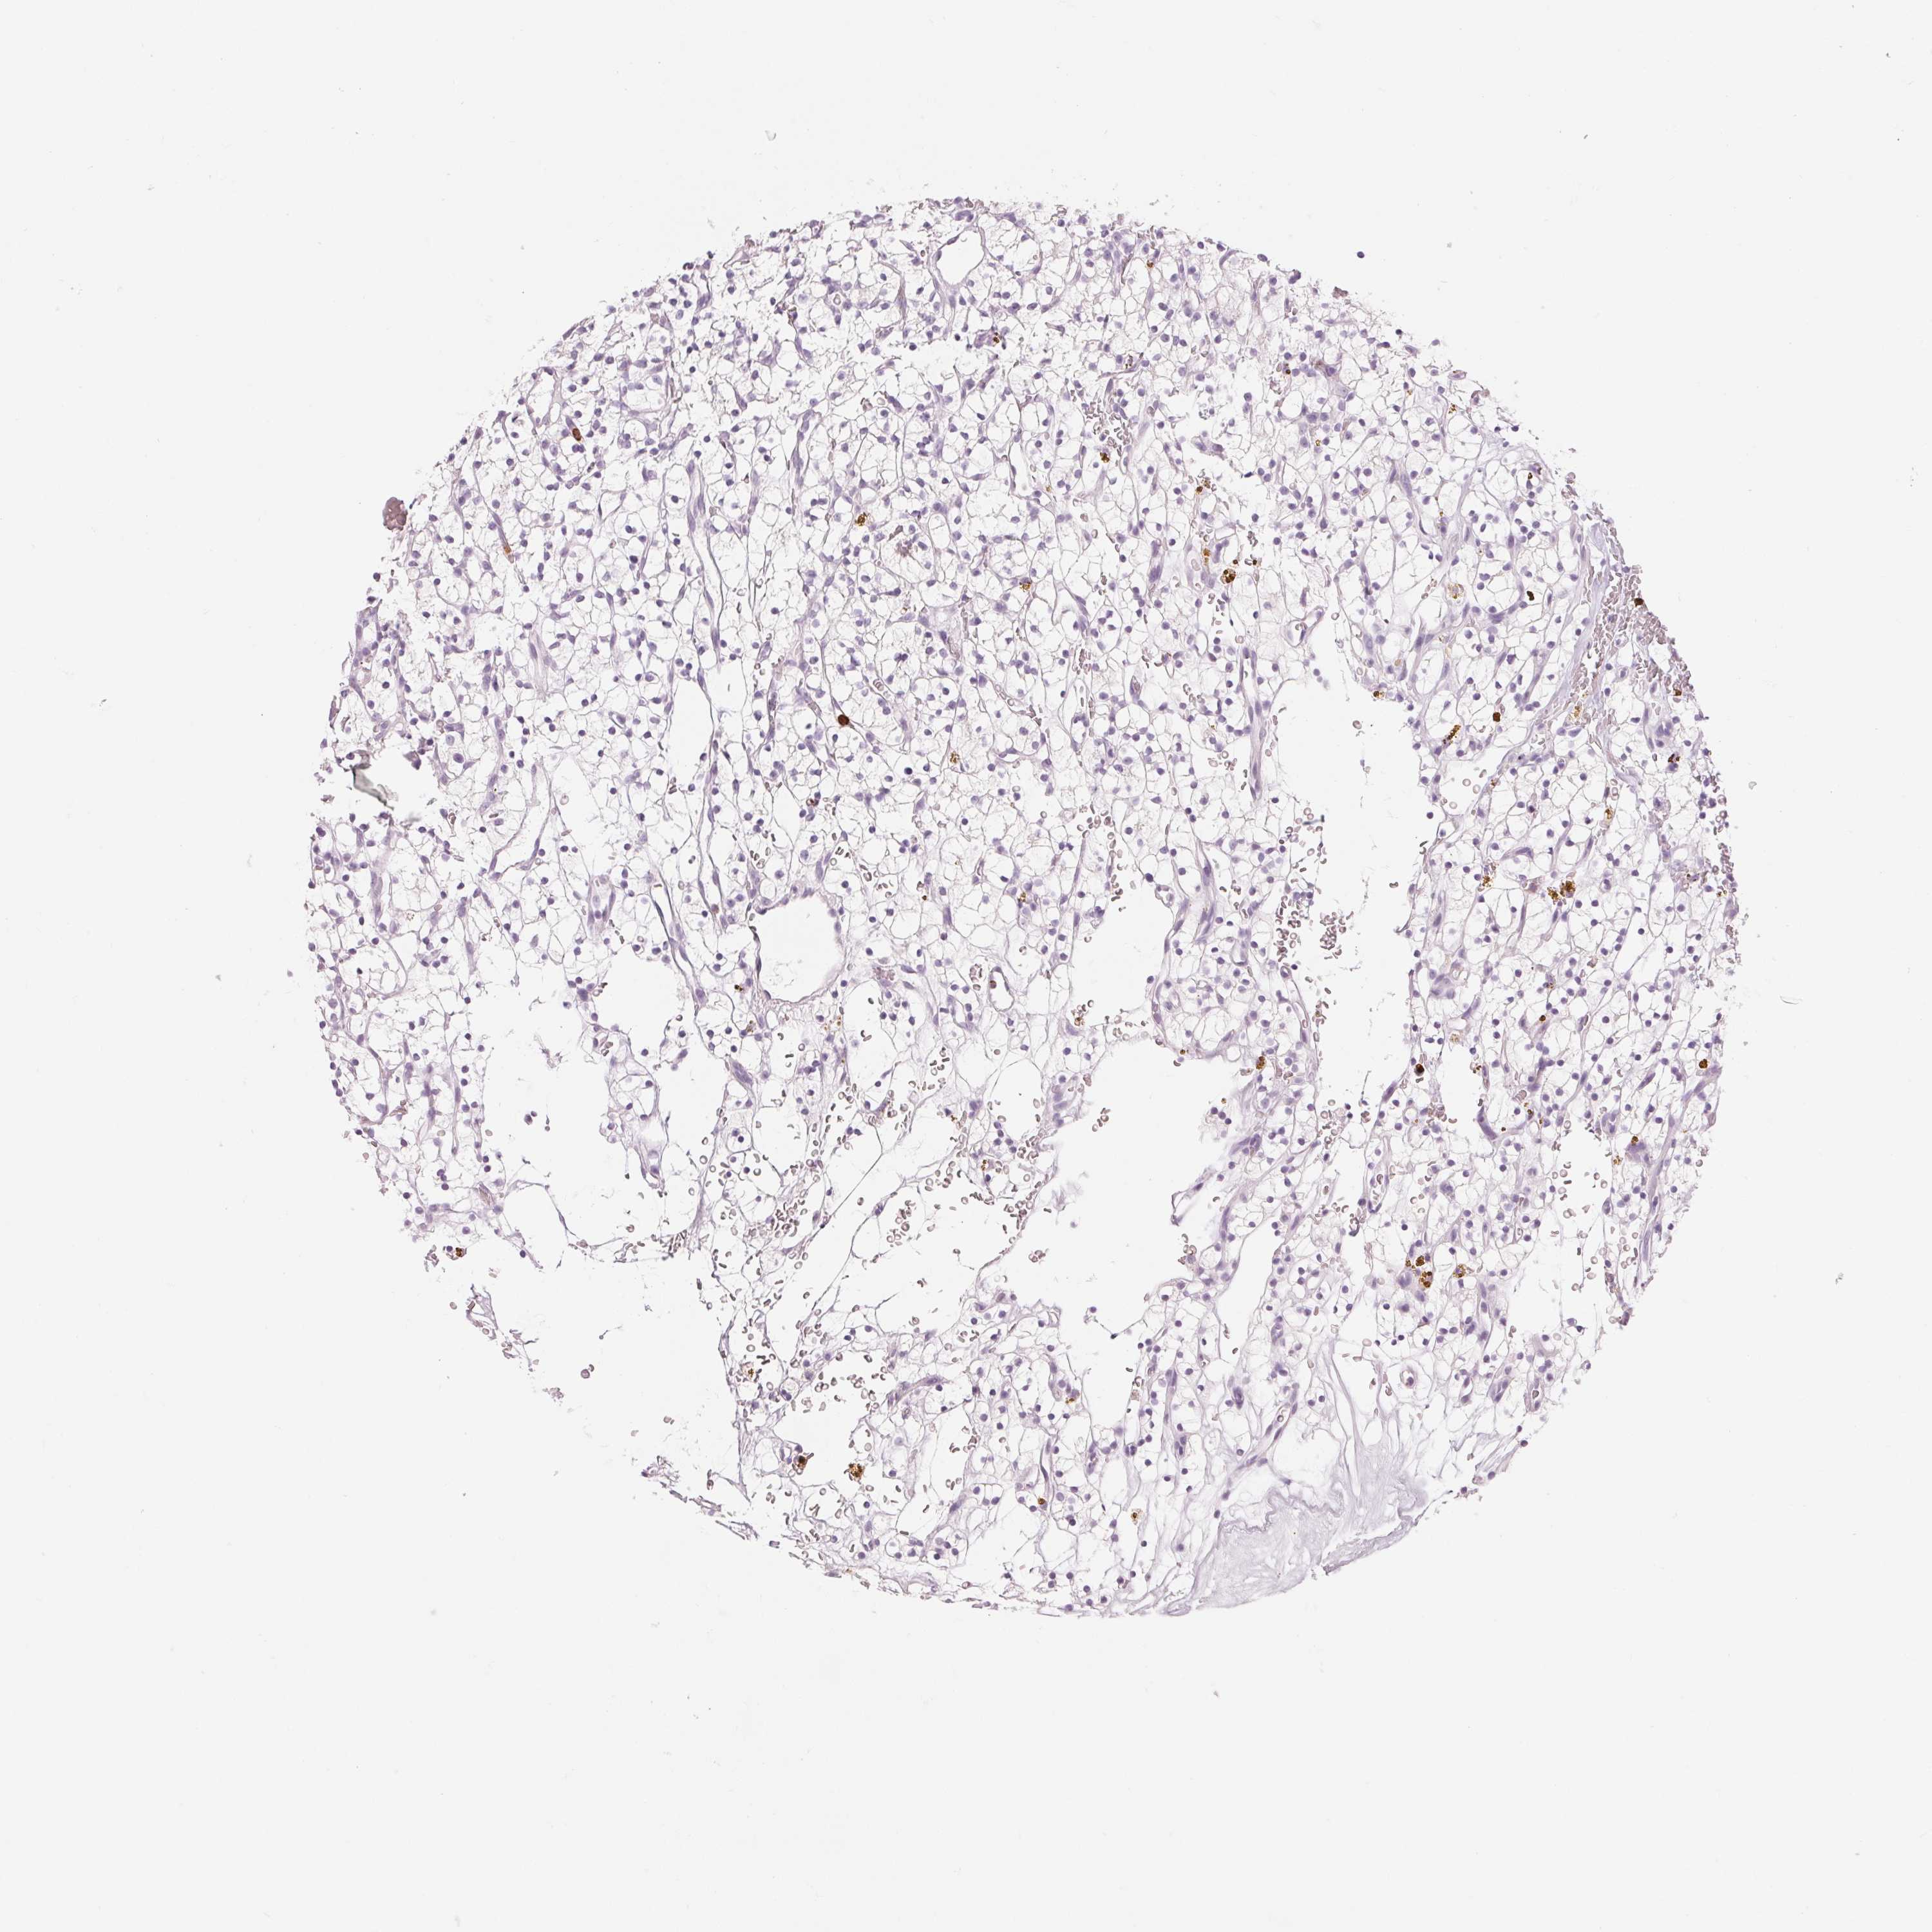

KIDNEY RENAL CLEAR CELL CARCINOMA (VALIDATION) - Interactive survival scatter ploti

The Survival Scatter plot shows the clinical status (i.e. dead or alive) for all individuals in the patient cohort, based on the same data that underlies the corresponding Kaplan-Meier plots. Patients that are alive at last time for follow-up are shown in blue and patients who have died during the study are shown in red.

The x-axis shows the expression levels (FPKM) of the investigated gene in the tumor tissue at the time of diagnosis. The y-axis shows the follow-up time after diagnosis (years). Both axes are complimented with kernel density curves demonstrating the data density over the axes. The top density plot shows the expression levels (FPKM) distribution among dead (red) and alive patients (blue). The right density plot shows the data density of the survived years of dead patients with high and low expression levels respectively, stratified using the cutoff indicated by the vertical dashed line through the Survival Scatter plot. This cutoff is automatically defined based on the FPKM cutoff that minimizes the p-score. The cutoff can be changed by dragging the vertical line or by entering a cutoff value in the square labeled "Current cut-off".

Under the Survival Scatter plot the p-score landscape (black curve; left axis) is shown together with dead median separation (red curve; right axis). Dead median separation is the difference in median mRNA expression between patients who have died with high and low expression, respectively. It is calculated as follows: median FPKM expression of dead patients with high expression - median FPKM expression of dead patients with low expression. This is intended to aid the user in visually exploring custom cutoffs and the associated p-scores and dead median separation.

Individual patient data is displayed and can be filtered by clicking on one or more of the category buttons on the top of the page. Categories describing expression level and patient information include: high, low, alive, dead, female, male and tumor stages. The scale of the x-axis can be toggled between linear and log-scale by clicking on the "x log" button. Mouse-over function shows TCGA ID, patient information and mRNA expression (FPKM) for each patient.

& Survival analysisi

Kaplan-Meier plots summarize results from analysis of correlation between mRNA expression level and patient survival. Patients were divided based on level of expression into one of the two groups "low" (under cut off) or "high" (over cut off). X-axis shows time for survival (years) and y-axis shows the probability of survival, where 1.0 corresponds to 100 percent.

KLK7 is not prognostic in Kidney Renal Clear Cell Carcinoma (validation)

TCGA RNA samplesi

RNA-seq data is reported as average FPKM (number Fragments Per Kilobase of exon per Million reads), generated by the The Cancer Genome Atlas (TCGA) .

Normal distribution across the dataset is visualized with box plots, shown as median and 25th and 75th percentiles. Points are displayed as outliers if they are above or below 1.5 times the interquartile range. FPKM values of the individual samples are presented next to the box plot.

Average pTPM 0.1

Number of samples 100